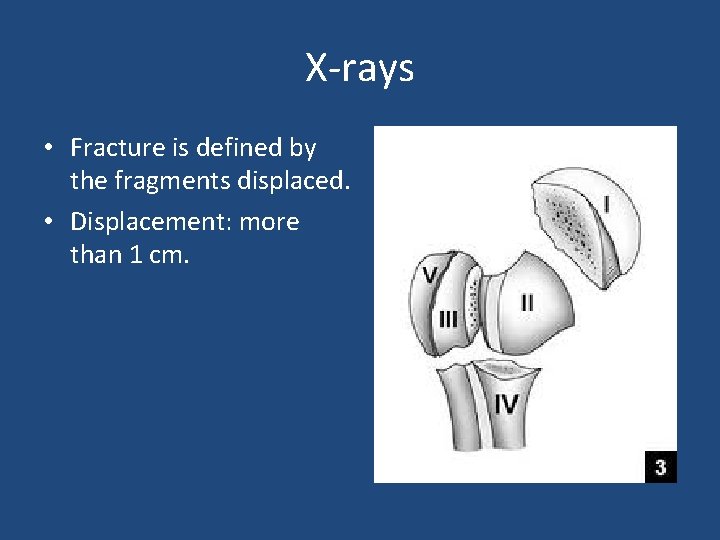

PROXIMAL HUMERUS ANATOMY • Proximal humerus has four anatomic parts: – – Head Greater tubrosity Lesser tubrosity Shaft • Anatomic neck v. s surgical neck.

X-rays • Fracture is defined by the fragments displaced. • Displacement: more than 1 cm.